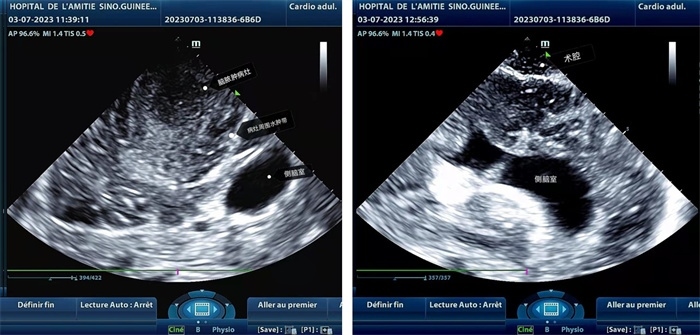

左圖顯示術(shù)中超聲見囊實性病變,大小約為4x4x3cm,病灶周圍腦組織水腫明顯;右圖為病灶切除后,術(shù)中超聲示術(shù)腔無病變殘留

左圖顯示術(shù)中超聲見囊實性病變,大小約為4x4x3cm,病灶周圍腦組織水腫明顯;右圖為病灶切除后,術(shù)中超聲示術(shù)腔無病變殘留。中國第二十九批援幾內(nèi)亞醫(yī)療隊供圖